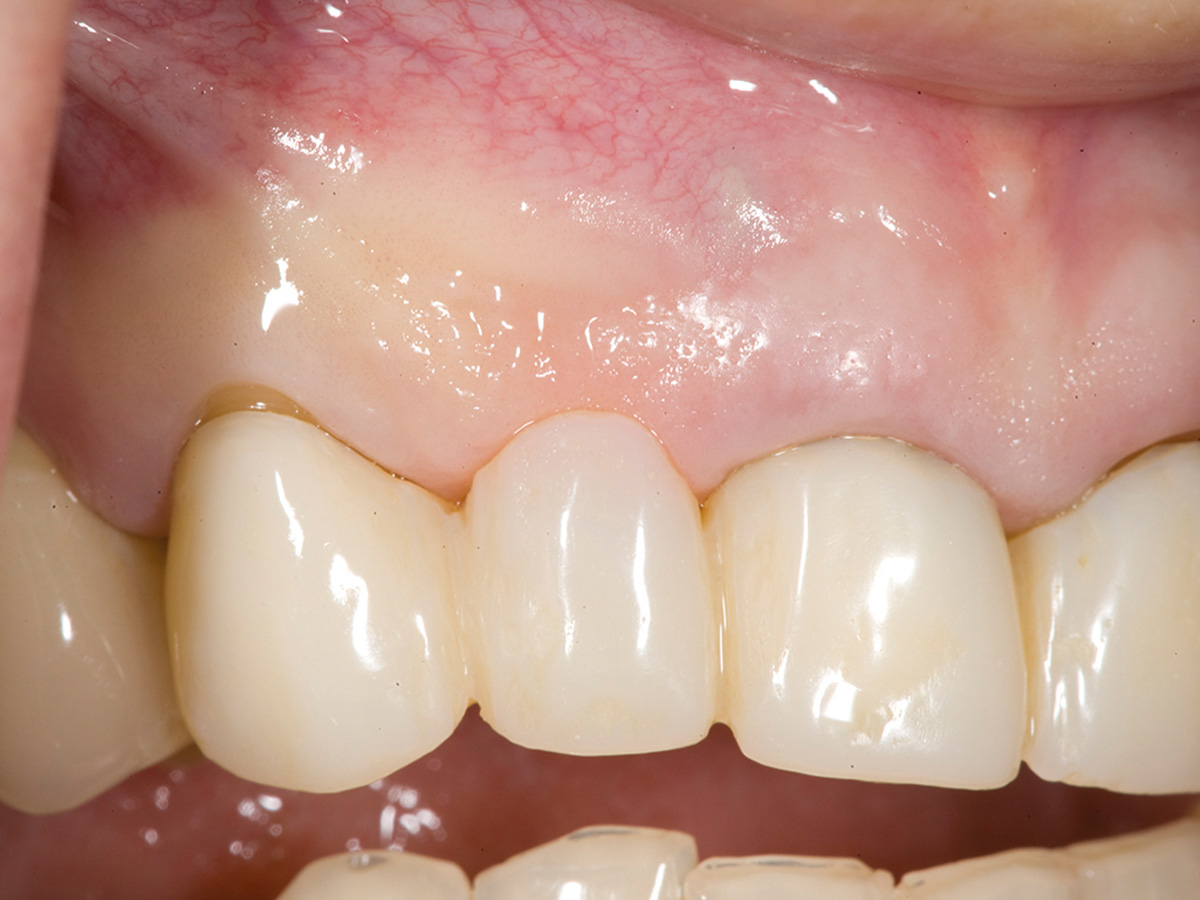

Abbildung 9

6 Monate post-OP nach Freilegung. Zu beachten ist der Alveolarkamm im Gegensatz zum Ausgangsbefund.